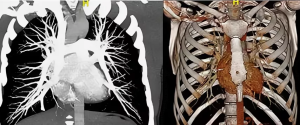

Мультипланарная 3D-peконcmpyкция: Перелом тела 8 - го ребра слева по средней подмышечной линии без смещения к/о. Переломы 9, 10, 11 -го ребер слева по лопаточной линии со смещениями к/о. Перелом хряща 1 - ребра справа без смещения к/о. Перелом головки 10- го ребра слева без смещения к/о (а), аксиальные срезы в легочном и костном режимах: уплотнение задне-базальных сегментов обеих легких (ушиб легких). Множественные переломы ребер (б, в).